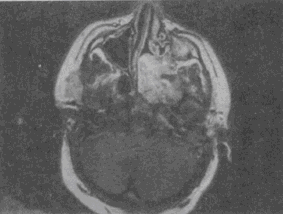

男,19岁,左侧鼻腔反复出血1年余,CT、MRI扫描如图,最可能的诊断是 YZ332_5_54_63.gif YZ332_5_54_63_1.gif YZ332_5_54_63_2.gif

• C.鼻咽部青年纤维血管瘤